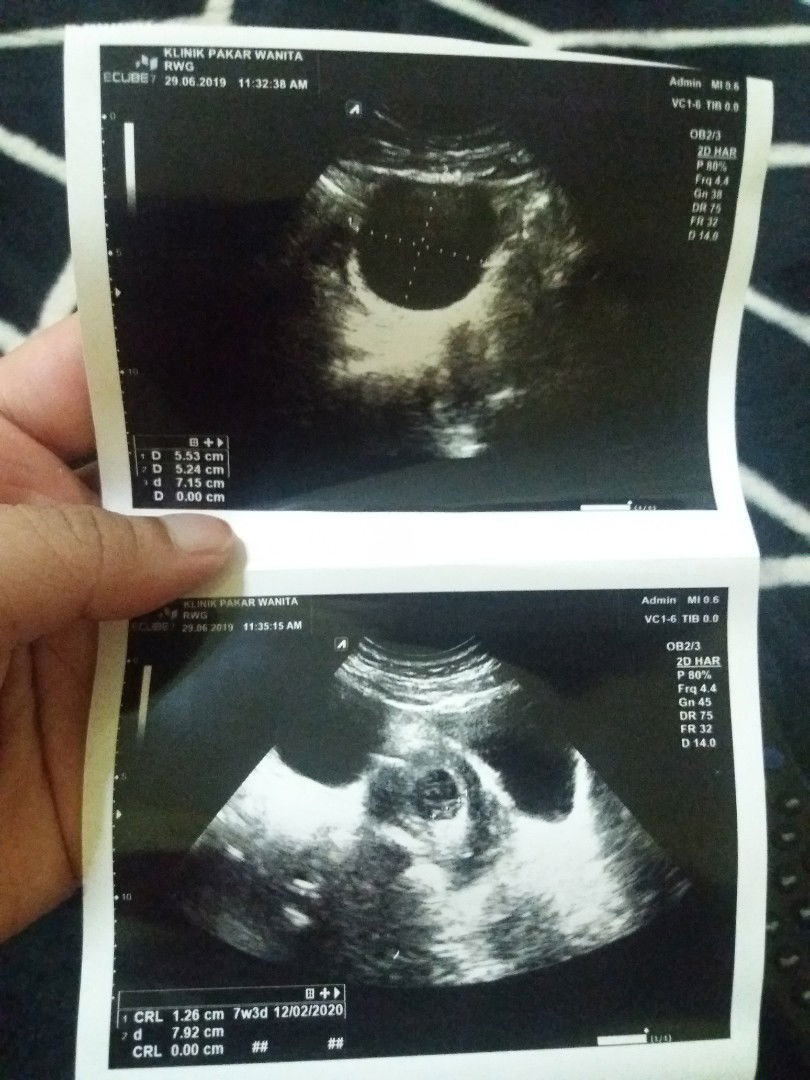

Cyst

25/6 bukak buku pink , 29/6 ada keluar darah terus g klinik pakar .. doc cakap ada cyst .. masa pergi bukak buku pink tu tak de pulak doc kata ada cyst ..bila pergi swasta doc cakap ada cyst saiz 5cm .. baby ok tapi risau bila cyst makin besar ?